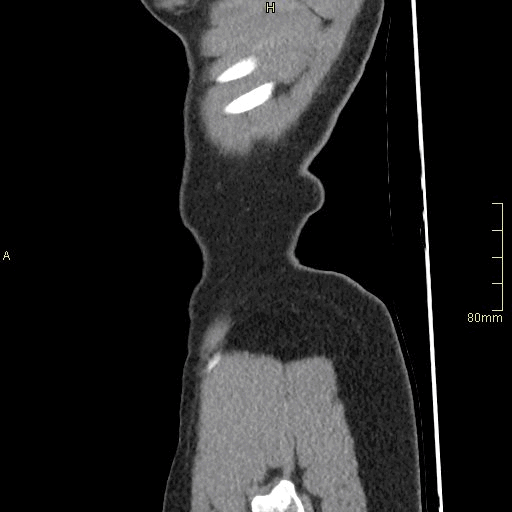

CTPA (Sagittal)

Portal Venous Abdomen (Sagittal)